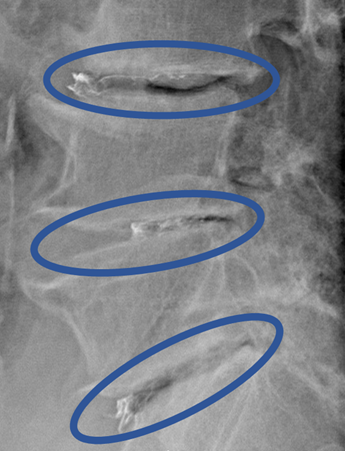

画像及び所見について

L1/2: 変性

L2/3: 変性、膨隆

L3/4: 変性、減高、脊柱管狭窄症、両側椎間孔狭窄

L4/5: 変性、減高

L5/S: 変性、膨隆

以上の事が画像上認められます。

L3/4、4/5、5/Sに椎間板変性、脊柱管狭窄症、椎間孔狭窄症を認め、主症状の原因の可能性が高い。

DiscoGelを入れた後の画像になります。